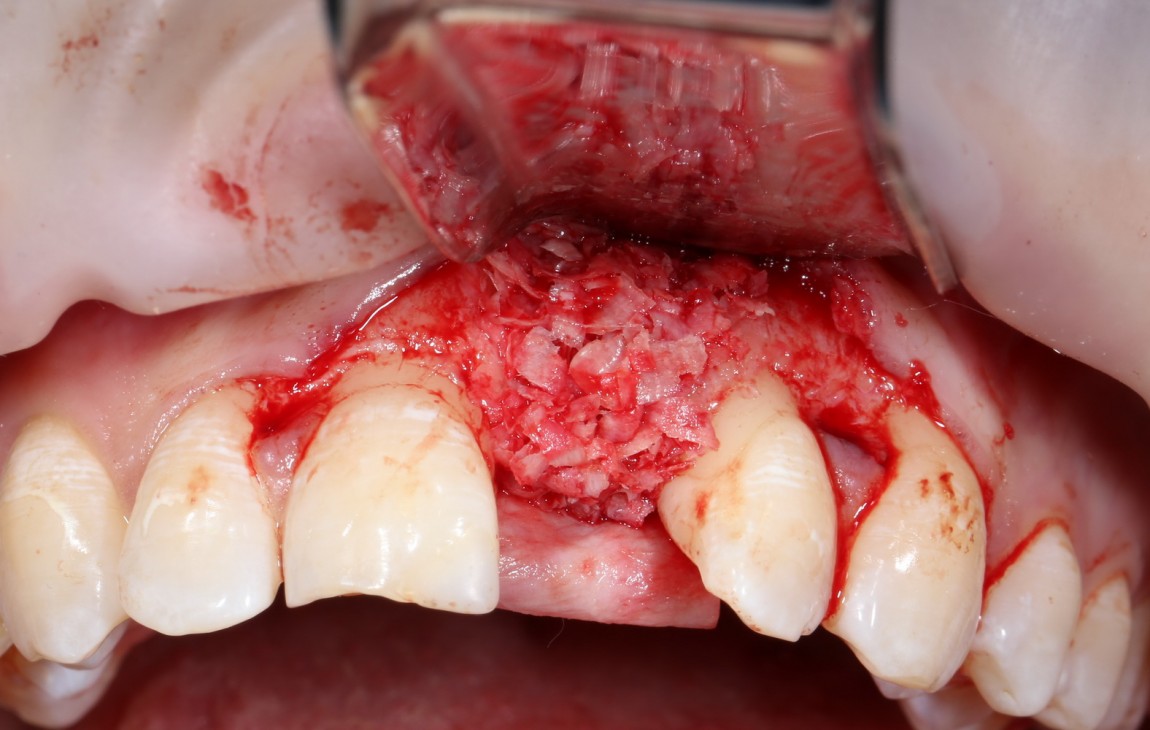

Итого, наиболее оптимальным в данной ситуации оказалась направленная тканевая регенерация с использованием барьерных мембран. В качестве барьерной мембраны у нас будет Geistlich BioGide. Ее очень легко адаптировать и позиционировать:

А в качестве трансплантата — аутокостная стружка, которую я насобирал заранее из области угла нижней челюсти:

Начну с того, что BioGide — это лучшее, что есть сейчас на рынке, а остальные мембраны ей завидуют. Как и в случае с макродизайном имплантов, именно физические свойства определяют как удобство использования, так и возможность достижения нужного результата. Прочность, эластичность, легкая адаптация и адгезия делают ненужными использование фиксирующих пинов. Мы просто закрываем мембраной графт — и все, можно накладывать швы:

В другом ракурсе видно, какой объем тканей мы восстанавливаем: